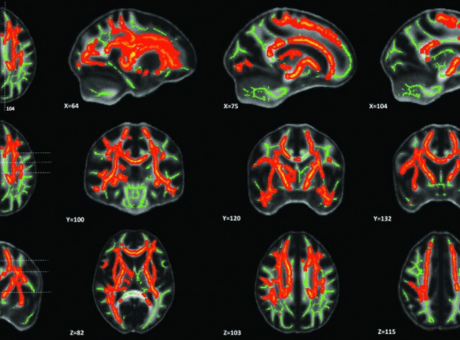

Pain-Related White-Matter Changes Following Mild Traumatic Brain Injury: A Longitudinal Diffusion Tensor Imaging Pilot Study

Cerebral white-matter tract regions of interest (ROIs). A common white-matter skeleton was first generated by the tract-based spatial statics (TBSS) toolbox in the FMRIB Software Library (FSL) using normalized diffusion tensor imaging (DTI) factional anisotropy maps from all the subjects. The white-matter skeleton was intercepted with Johns Hopkins University (JHU) white-matter tract atlas, and eighteen ROIs were used in this study.